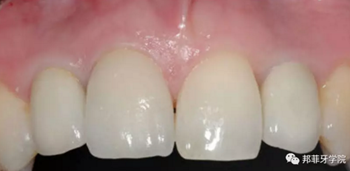

6年后效果穩(wěn)定,患者滿(mǎn)意(圖16)。

圖 16-1: 六年后復(fù)查

圖 16-2: 六年后復(fù)查